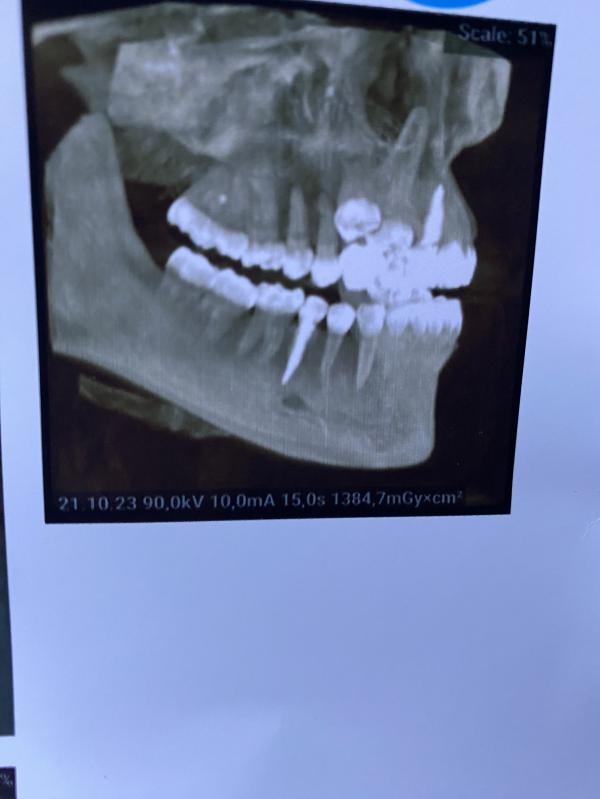

Девочки, первый раз делала кт челюсти. Что такое белое вторым рядом сверху? Комплект вторых зубов?)

Сверхкомплект)) Всякое бывает, у нас была пациентка, у нее двойки верхние были молочные, постоянных зачатков не было. Тоже женщина 35-40 лет